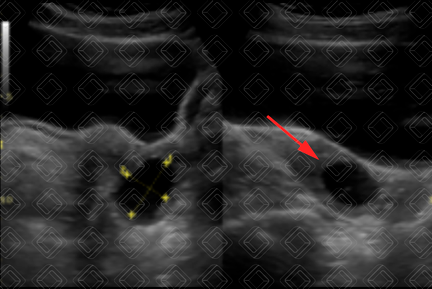

Descrição das figuras 7, 8 e 9: Paciente de 35 anos, feminina. Ultrassonografia da pelve, estudo via transvaginal, evidenciando lesão hipoecoica, com ecos internos em suspensão e discretos nódulos hiperecogênicos parietais, sem fluxo ao Doppler colorido, sugerindo endometrioma (seta vermelha); lesão foi ressecada e seu diagnóstico confirmado.

Endometrioma (figuras 7, 8 e 9): Na ultrassonografia, são lesões císticas hipoecoicas, habitualmente homogêneas, com finos ecos internos e pequenos focos ecogênicos parietais (vale ressaltar que não deve haver vascularização nestes pequenos nódulos).